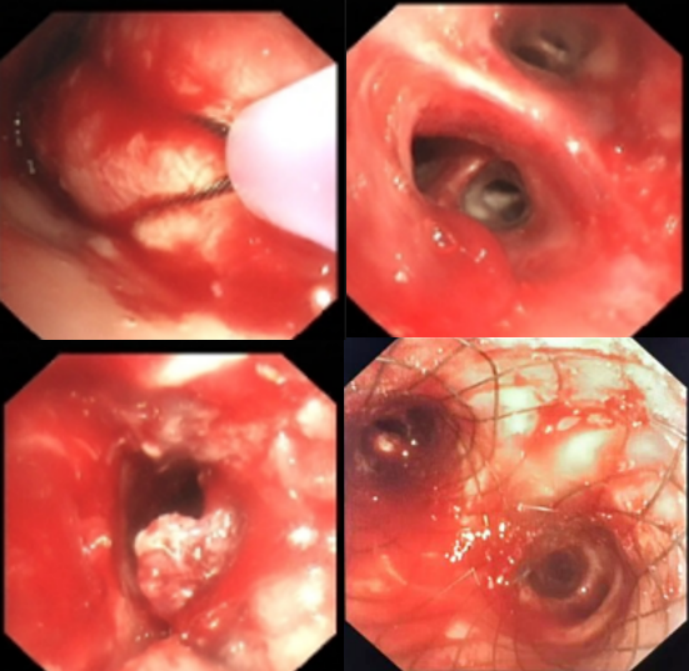

六、VV-ECMO的拓展应用

VV-ECMO的应用已不再局限于传统的呼吸衰竭救治,还可作为综合介入治疗的保驾手段。例如,某63岁男性患者,活动后气喘1周,胸部CT提示左肺、右肺中叶感染性病变,左肺门区肿块影伴左主支气管闭塞,左侧大量胸腔积液,诊断为食管癌晚期。在VV-ECMO保驾下实施介入治疗,开放气道并植入支架(图4),术后患者顺利恢复。该病例体现了VV-ECMO在复杂重症患者救治中的拓展价值。但此类应用需严格评估患者病情及团队救治能力,权衡利弊后谨慎实施。

图片

4  患者在ECMO支持下行介入治疗